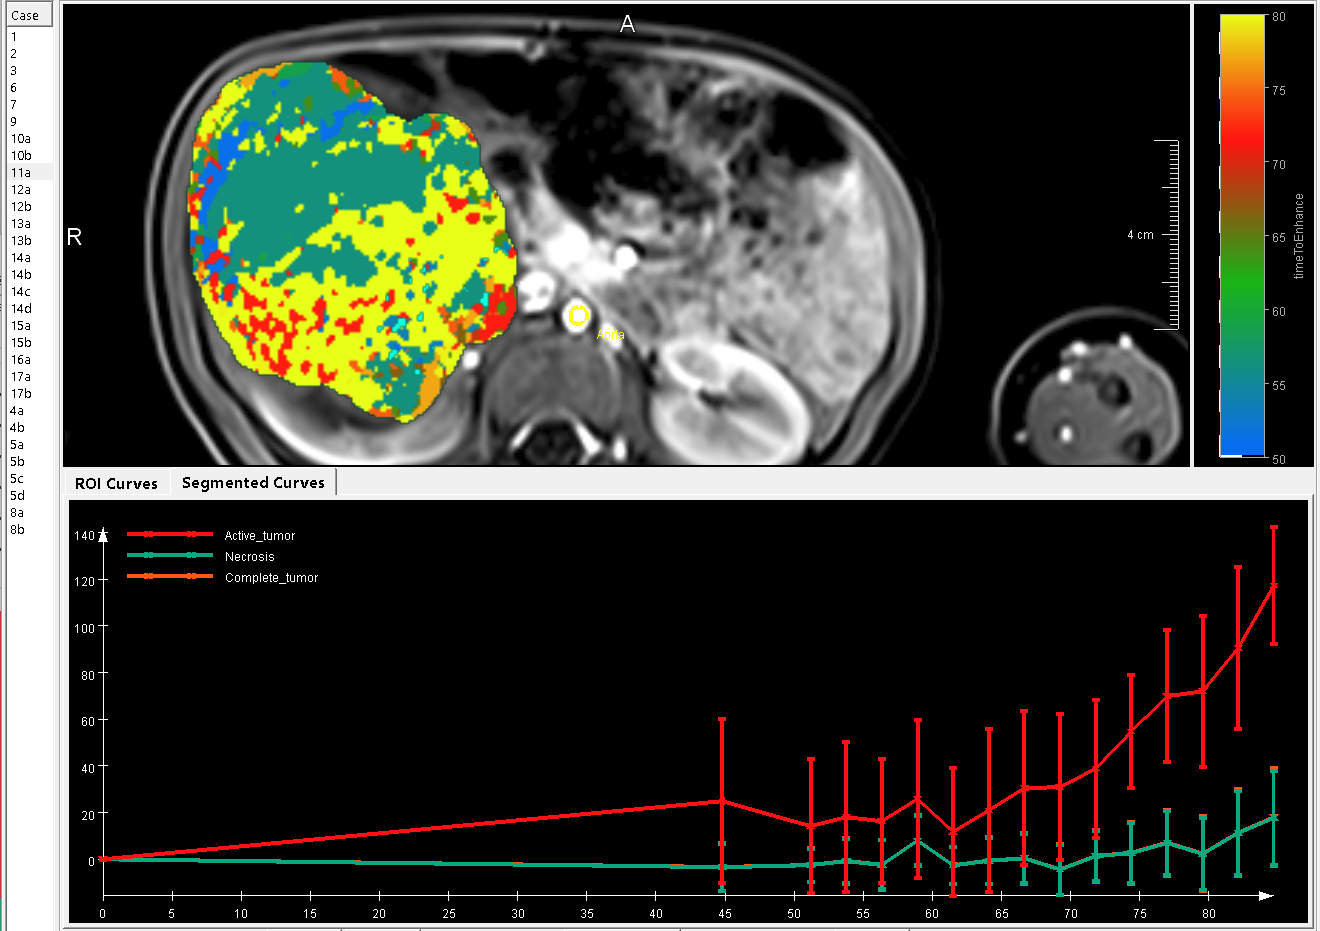

The experts of the Fraunhofer Institute for Digital Medicine MEVIS are looking forward to welcoming you at their booth A10.

At this year's GPR Fraunhofer MEVIS presents the following topics: